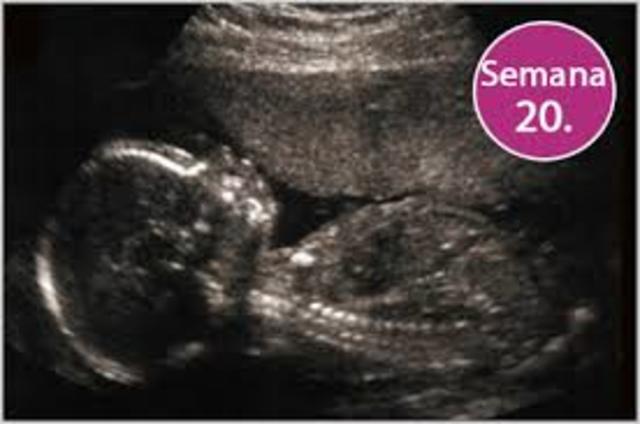

• 20 SEMANA

20 SEMANA

el feto pesa entre 280gramos y 350 gramos, aproximadamente el 10% del peso que tendrá al nacer. El vello, llamado lanugo, se distribuye por casi toda la piel. El feto se pone el pulgar en la boca desarrollando más el reflejo de succión. Cuando la madre descansa el bebé se mueve, porque no tiene presión externa, y a la inversa, cuando la madre se mueve se acurruca para protegerse y no lastimarse.